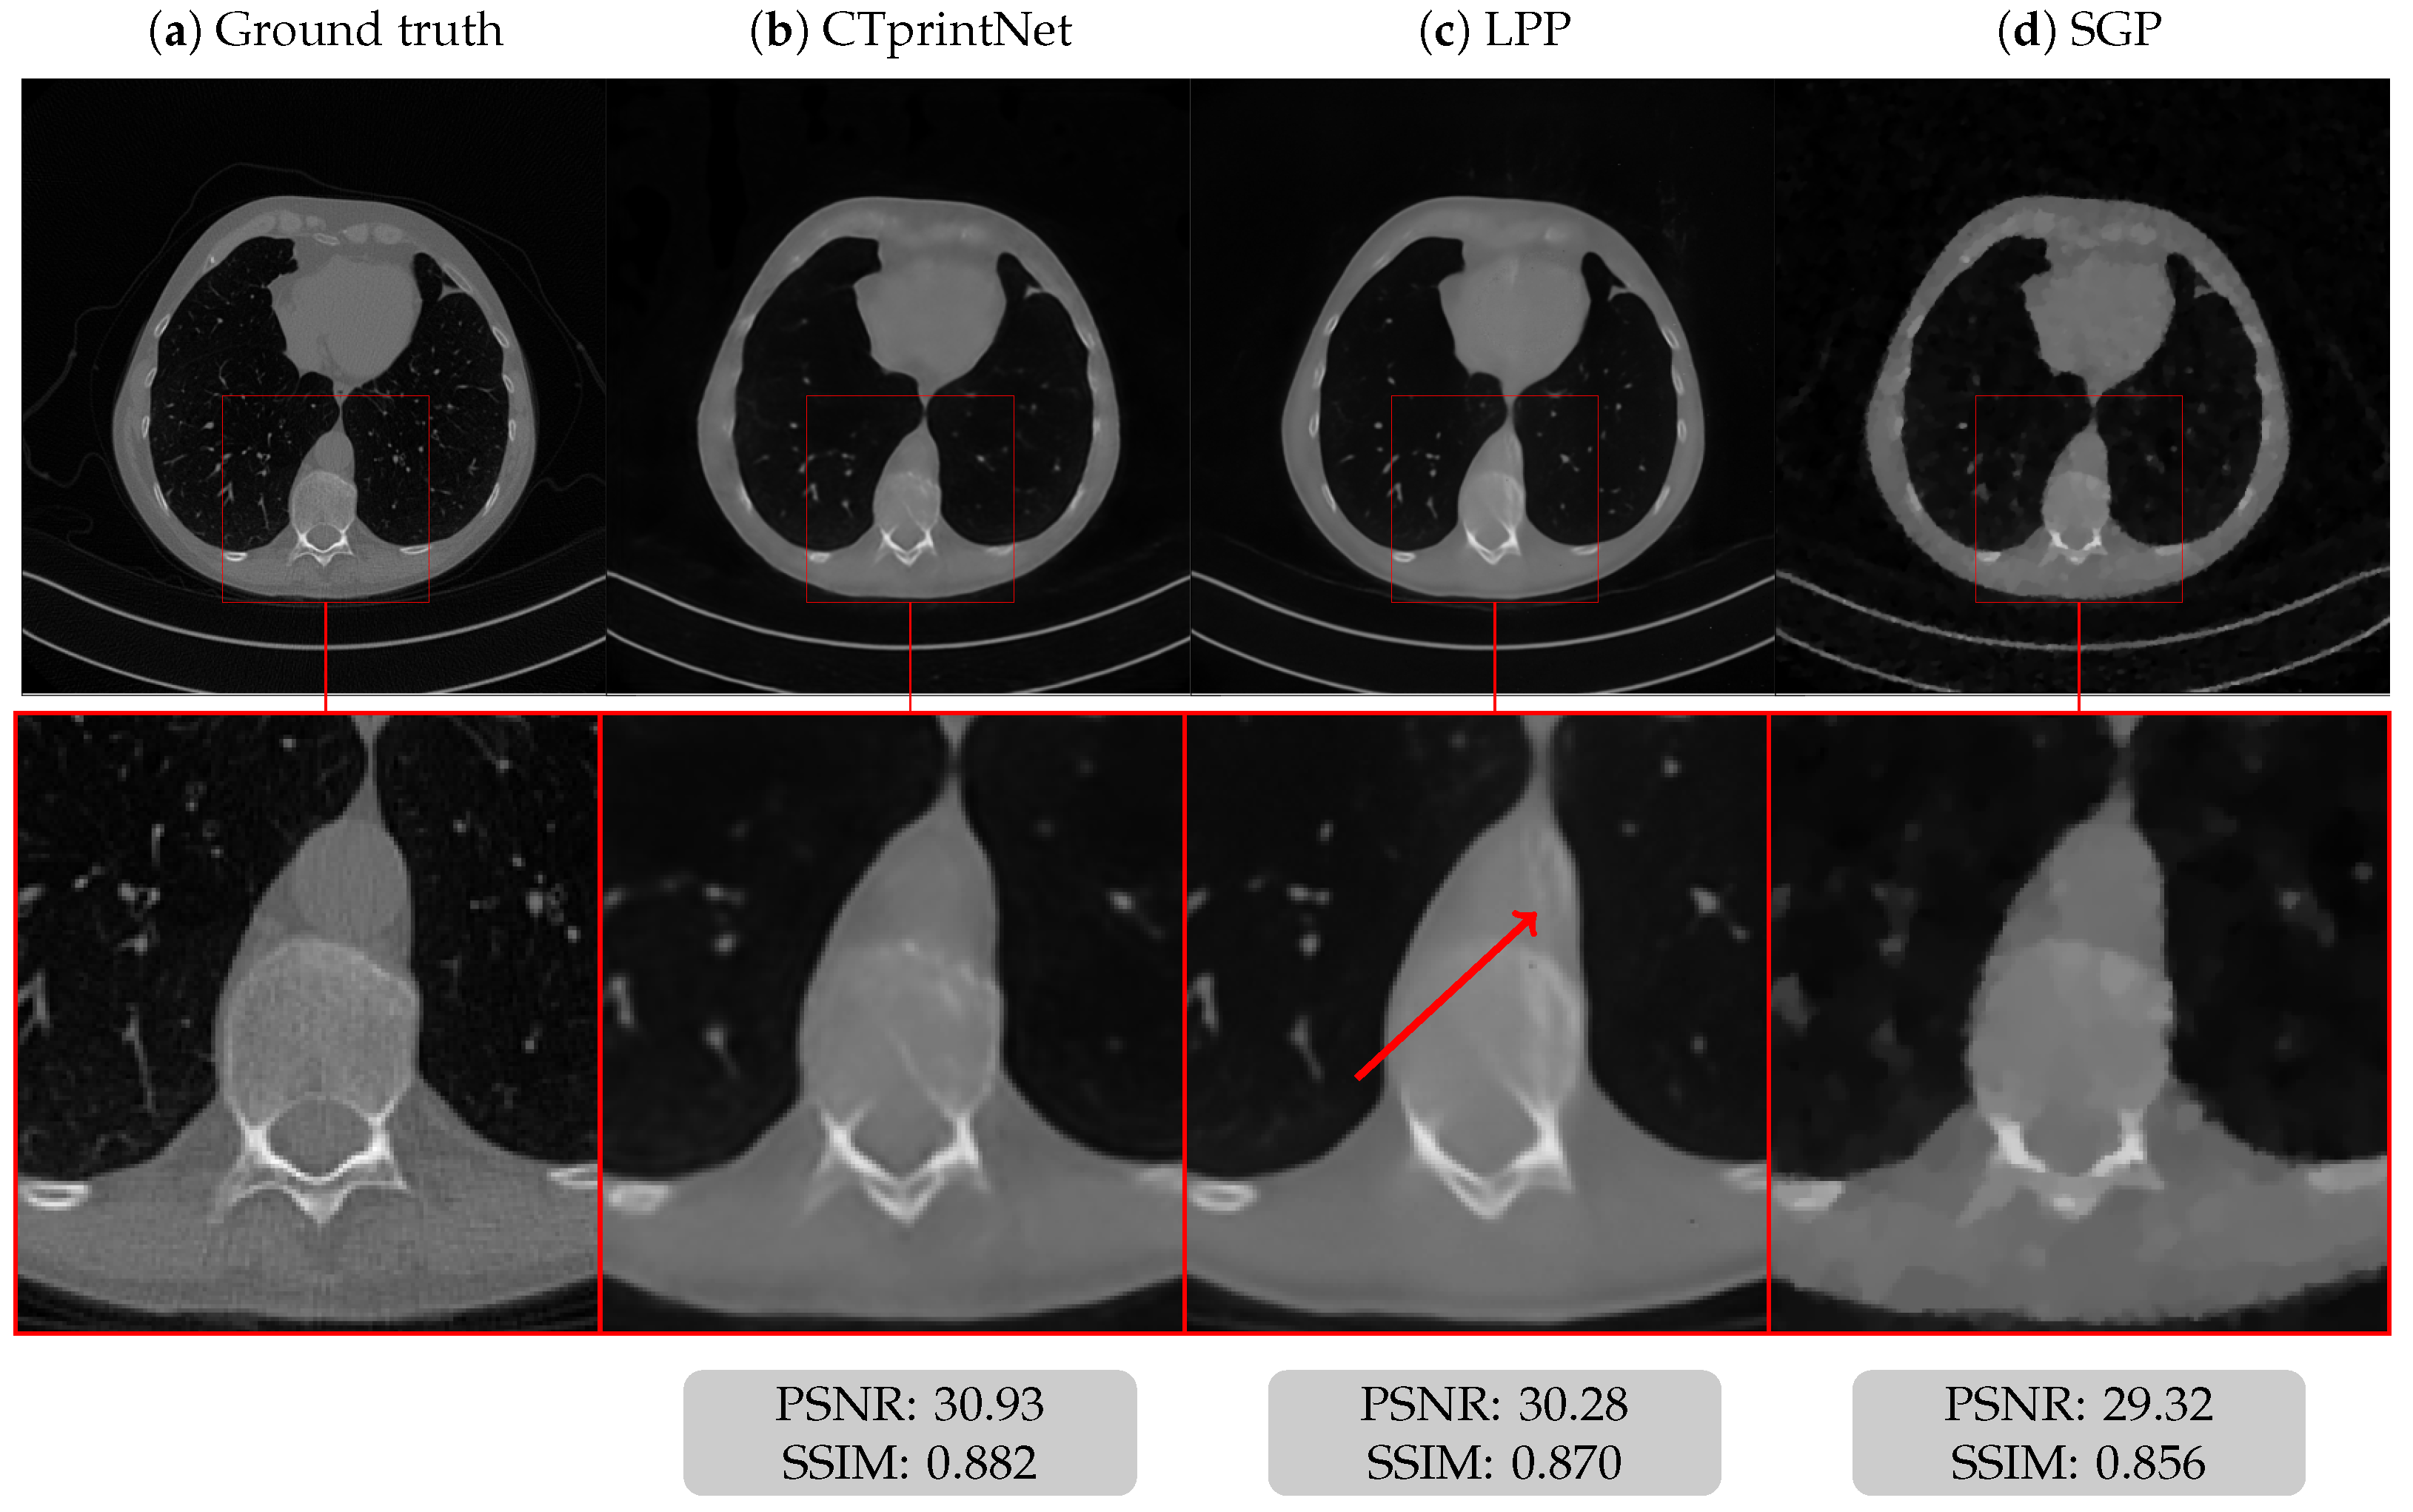

5.1. Results on a Synthetic Dataset

5.3. Results on a Realistic Dataset